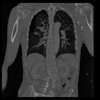

29 CUERPO,CE,Coronal,3.000,CUERPO,Coronal,